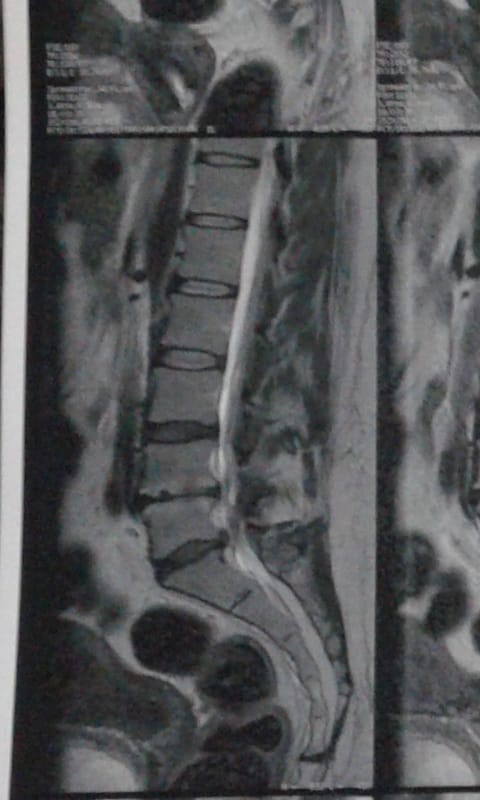

Peço ajuda para realizações de exames, tratamento e cirurgia devido complicações da coluna lombar, hérnias de disco e desgaste que comprometeu a sustentação do assoalho pélvico que é o músculo que sustenta intestino e bexiga. Por este motivo o uso da sonda vesical e fraldas. Agradeço a todos(as) qualquer ajuda será bem vinda ! Obrigada e que Deus abençoe a cada um de vocês. –  escreveu Claudia Cardoso.

A mulher em conversa com a reportagem pediu e faz questão de mostrar seus exames e o parecer médico: